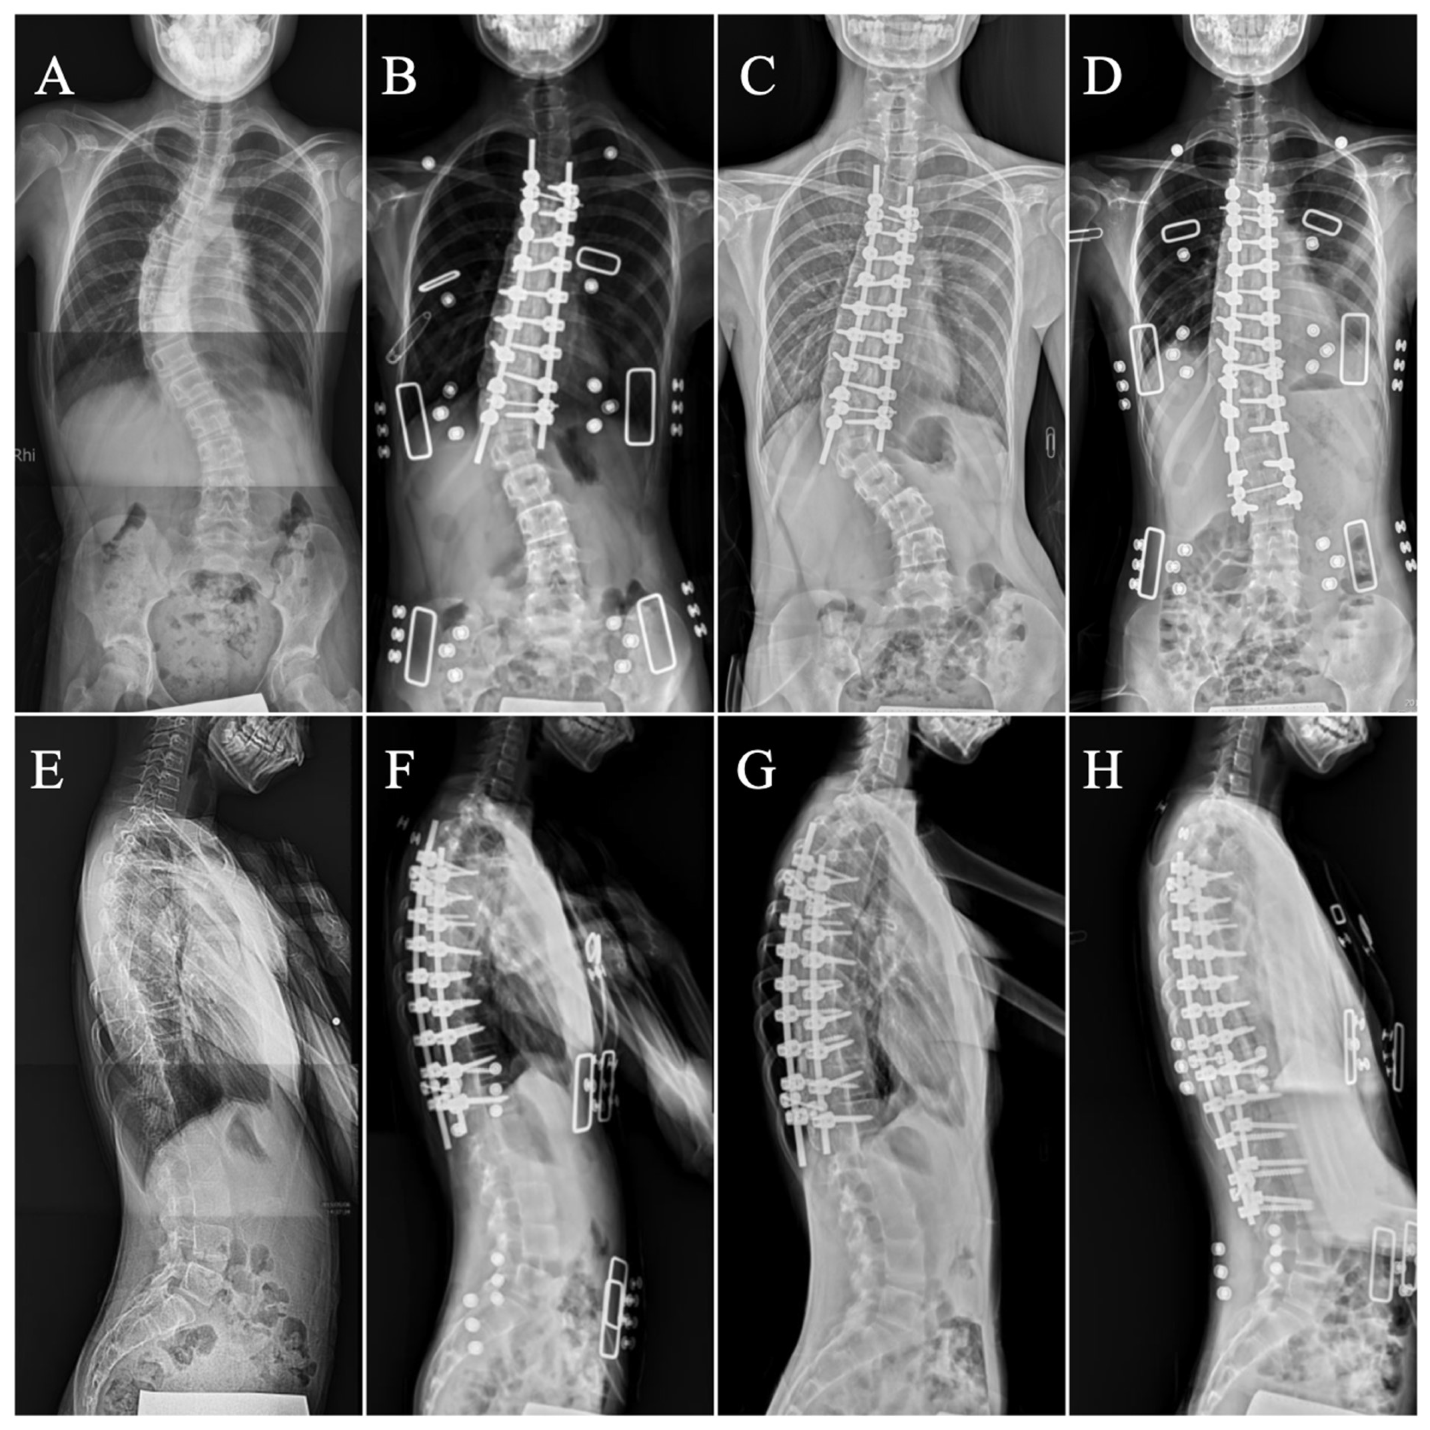

2.4. Surgical Procedure and Postoperative Care

2.5. Measurements

3. Results